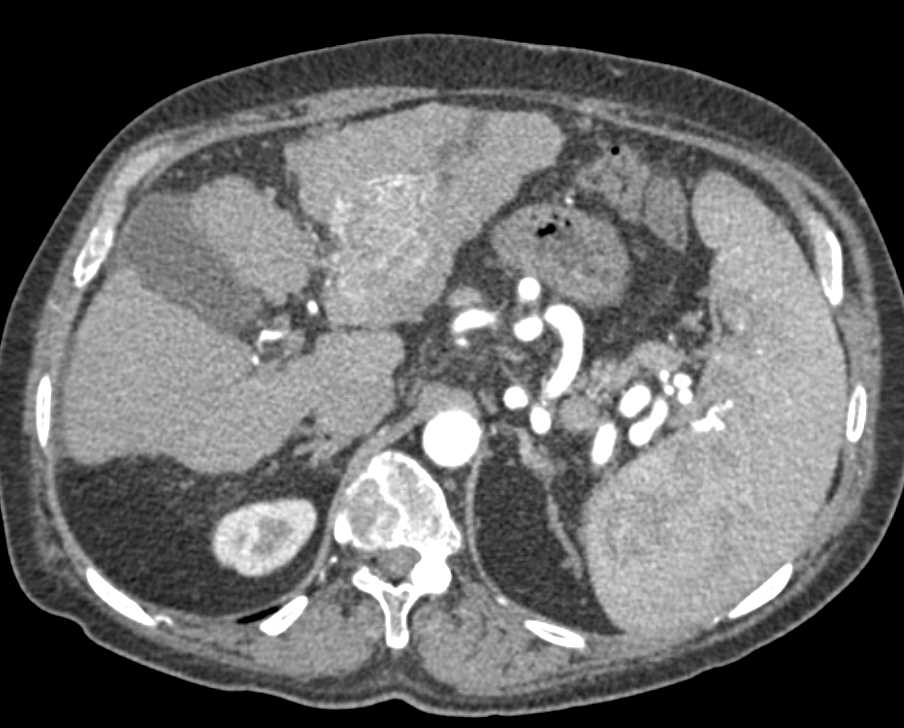

Renal Cell Carcinoma Involves the Renal Vein